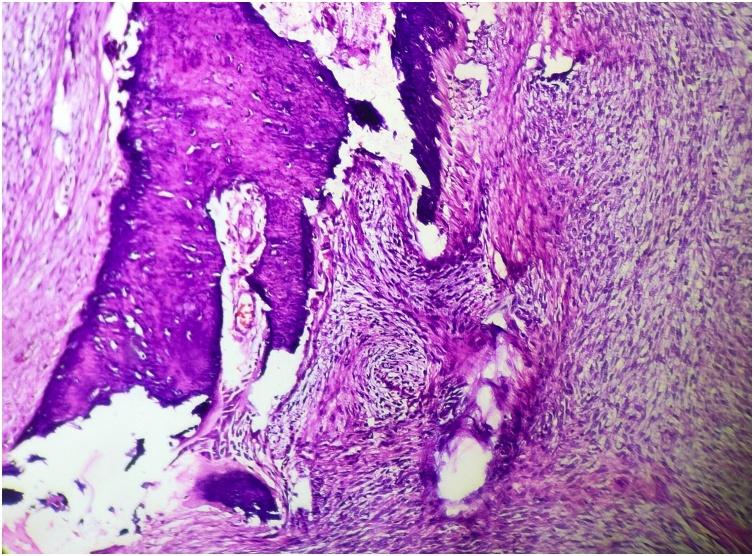

A 48 year old female presented initially with a localised swelling of 2 cms diameter in the front of the left elbow in 2007, which was excised. It recurred repeatedly and was excised. In the earlier presentations, the swellings were firm, mobile and not fixed to bone. In the last stage alone, bone fixity was identified. All the fourteen surgeries were performed by the primary author from 2007 to 2020, as the patient was particular. THE MAIN CLINICAL DIAGNOSES: had been neurofibroma and fibrosarcoma. There was no evidence of distant metastasis all these years. She did not respond to radiation or chemotherapy. Initially it was single, but later multiple. She had no clinical features of Neurofibromatosis 1 (NF1) or any family history. As the history progressed, the swellings became muscle deep and later encircled the radial nerve. The radial nerve was salvaged on three occasions. On the last three occasions, the tumour had to be shaved off from the humerus. The final amputation specimen showed a single tumour infiltrating the humerus and x-ray revealed bone destruction and tumour calcification. Final diagnosis was aided by immunohistochemistry (IHC) and cytogenetic study (FISH).

一名48岁女性于2007年首次就诊,左肘前部出现一个直径2厘米的局限性肿块,该肿块被切除。它反复复发并被切除。在早期表现中,肿块质地坚硬、可活动,未与骨骼固定。仅在最后阶段才发现与骨骼固定。从2007年到2020年,所有14次手术均由第一作者进行,因为患者比较挑剔。主要临床诊断曾为神经纤维瘤和纤维肉瘤。这些年来均无远处转移的证据。她对放疗或化疗均无反应。最初是单发,但后来变为多发。她没有神经纤维瘤病1型(NF1)的临床特征或任何家族史。随着病程进展,肿块深入肌肉,后来环绕桡神经。桡神经曾三次得以保留。在最后三次手术中,不得不从肱骨上刮除肿瘤。最终截肢标本显示单个肿瘤侵犯肱骨,X线显示骨质破坏和肿瘤钙化。免疫组织化学(IHC)和细胞遗传学研究(FISH)辅助做出了最终诊断。